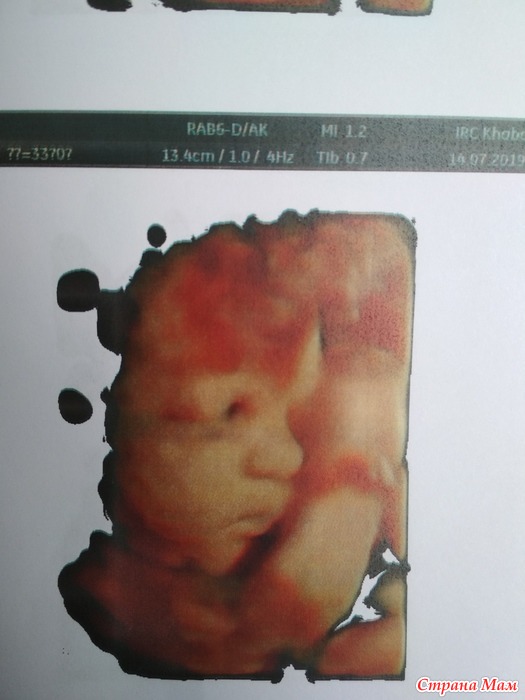

Вчера был 3 скрининг.

А какой он милый и сладкий, я аж таю. Улыбнулся нам с папкой

Муж и врач узист сказали копия мамы - сын. Значит у меня одинаковые детки в животе растятся)) посмотрим.